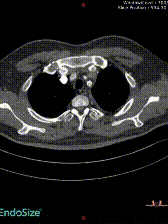

随访评估:术后第6天随访显示远端塑形良好

即刻效果:术后患者肌力恢复至2级